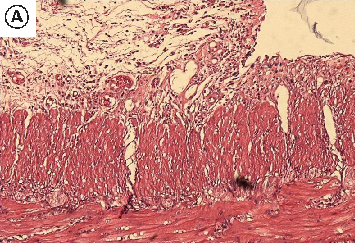

Figure 4

The Healing Effect of Aloe Vera Gel on Acetic Acid-Induced Ulcerative Colitis …